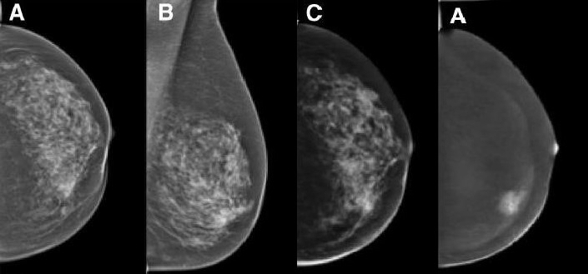

Imaging and Targeted Biopsy of Breast Cancer

Martin Daniaux

Dual-energy (DE) contrast-enhanced mammography is one of the latest developments in breast care. Imaging with contrast agents in breast cancer has been described in MRI and CT. However, high costs, limited availability and high radiation doses have led to the development of contrast-enhanced spectral mammography (CESM).

The research team focusing on the diagnosis of breast cancer has a vast wealth of experience with all the imaging modalities currently used for evaluation of the breast, including fine-needle aspiration and/or percutaneous biopsies using stereotaxis or ultrasound guidance. Our unit serves as the largest screening and assessment centre of the national breast-screening programme in Tyrol. Approximately 10,000 mammograms and breast ultrasound studies are performed each year.